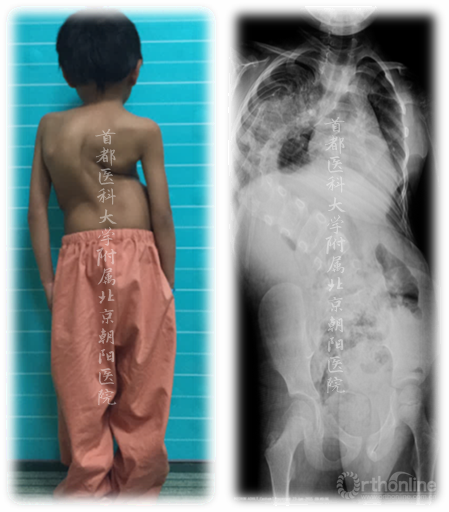

先天性:

● 是指在子宫内椎体未正常发育的一种EOS类型。

■ 先天性脊柱侧凸有时伴随有心脏和肾脏的异常。进行评价时可能要包含有关心脏和肾脏方面的检查。

椎体发育异常

Congenital:

● A particular type of EOS in which the vertebrae develop incorrectly in utero.

■ Congenital scoliosis is sometimes associated with cardiac and renal abnormalities. Evaluation may include studies of heart and kidneys.